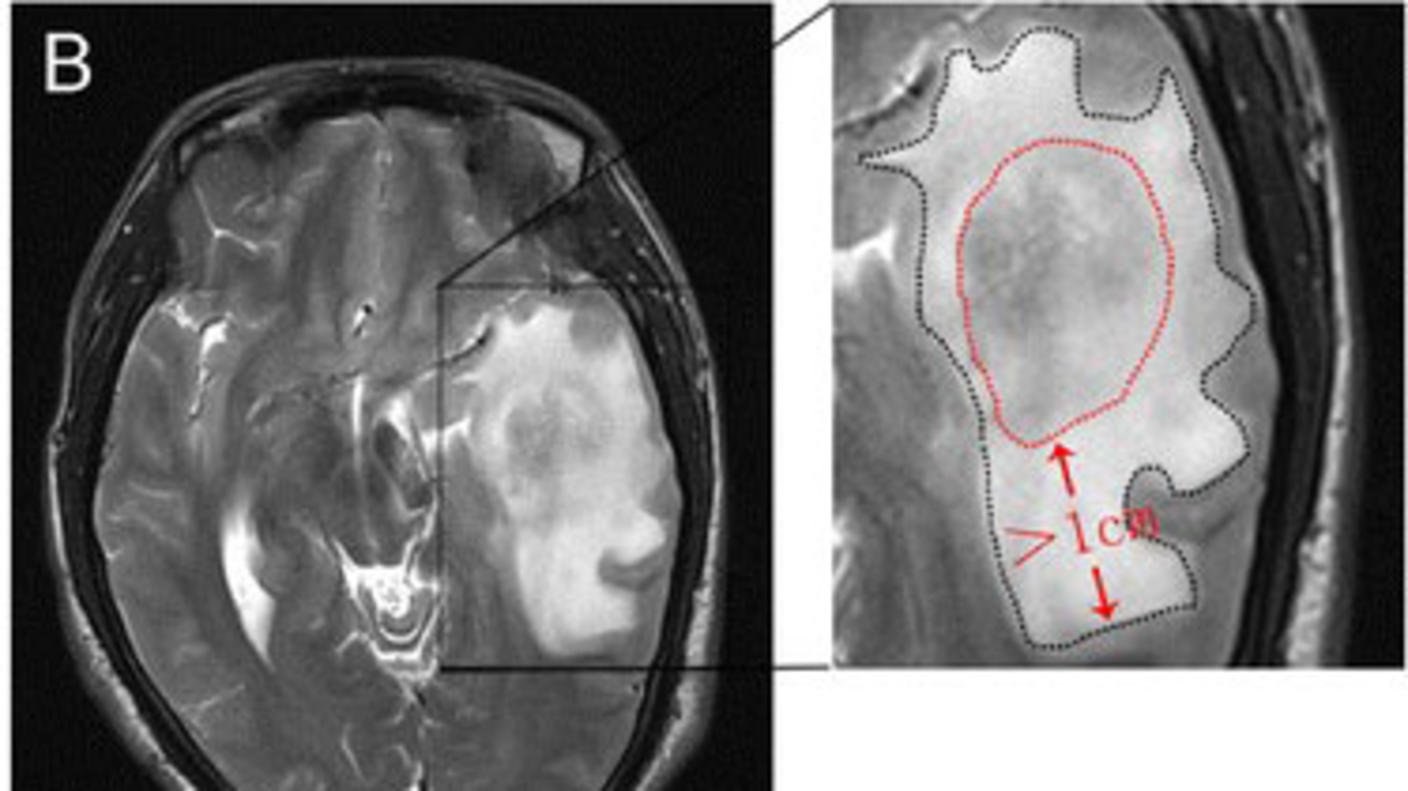

To better understand how some glioblastoma cells might be taking advantage of neuroplasticity, the researchers analyzed tissue samples taken from areas of people’s tumors that had high neural activity in response to language tasks and compared them to areas with low activity.

They found that a subset of tumor cells from areas with high functional connectivity and neuronal activity had an uptick in the expression of genes involved in assembling new neural circuits. This included a sevenfold increase in expression of a gene called THBS1, which directs cells to create a protein called TSP-1. TSP-1 is normally produced by healthy astrocytes in the brain and encourages the growth of new synapses.

Overall, about 2.5% of glioblastoma cells from the samples tested expressed THBS1, and cells from areas with high functional connectivity had higher levels of THBS1 expression than areas with low functional connectivity. Microscopy techniques confirmed that a subgroup of tumor cells in areas with high connectivity produced TSP-1, and that these areas formed more new synapses.

The presence of neurons also made tumor cells from areas of high connectivity behave more invasively. For example, the team found that mice implanted with tumor cells derived from areas of high connectivity developed larger tumors and died sooner than mice implanted with tumor cells derived from areas of low connectivity.

The danger posed by tumors that manipulate neural connections seemed to hold for people as well.

When the researchers looked at 44 people with glioblastoma who had undergone surgery, those with tumors that showed many connections with surrounding neurons lived about a year less than people whose tumors lacked these connections (an average of 71 weeks versus 123 weeks). People whose tumors had high connectivity with surrounding neurons also had more trouble using language, a sign of worse overall cognitive functioning.